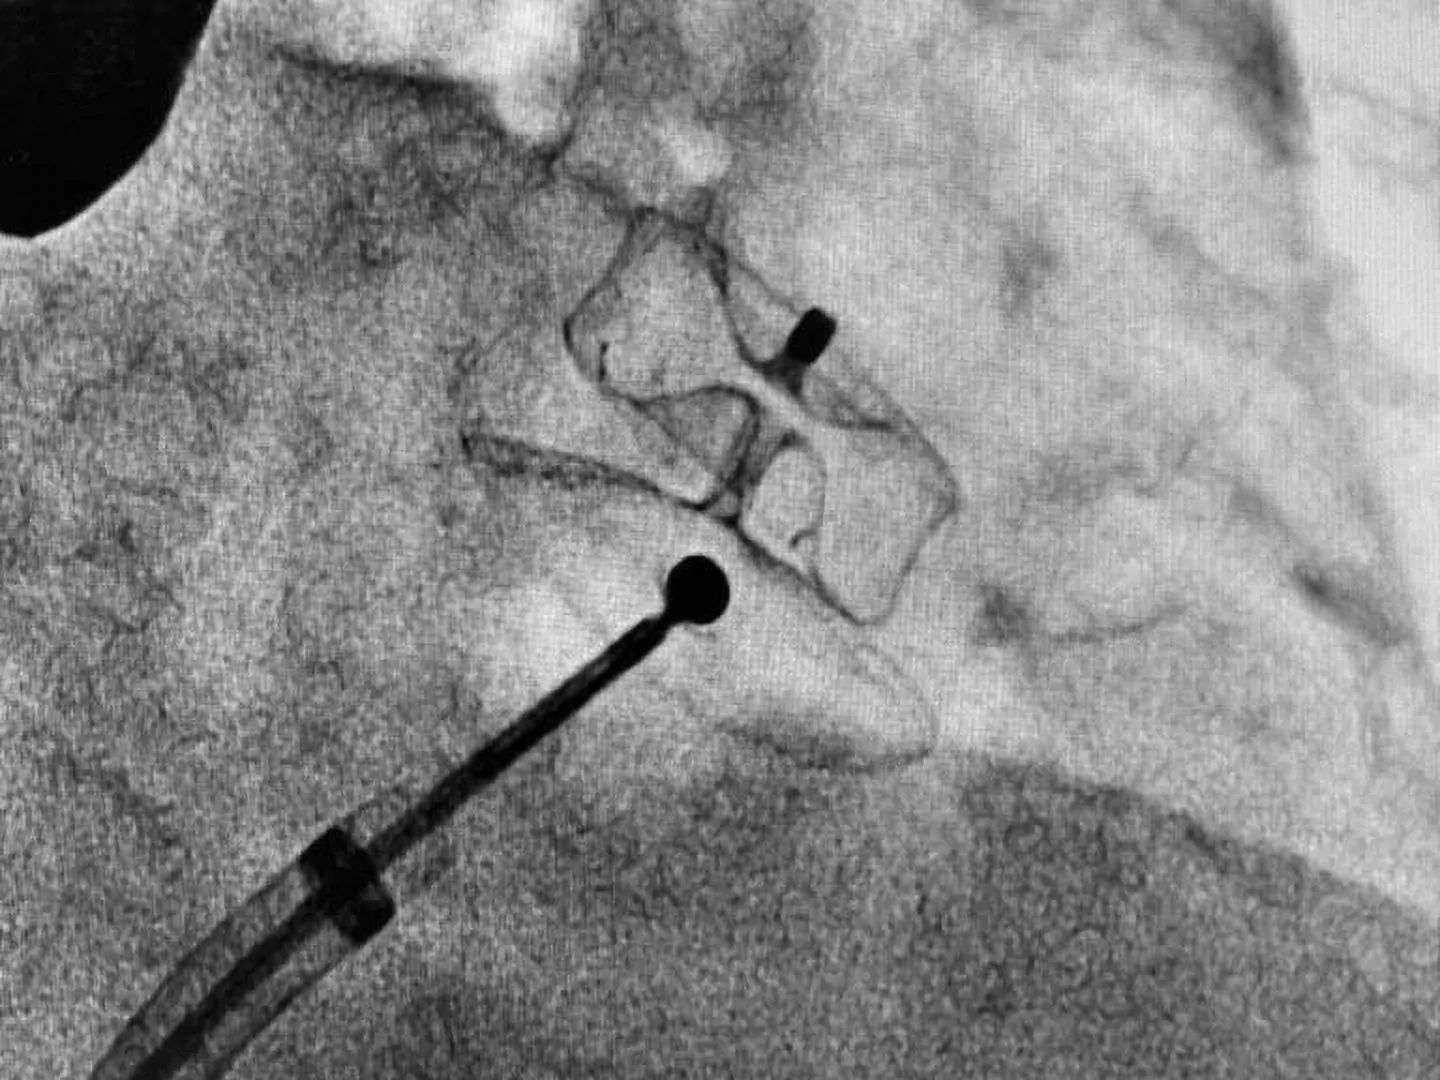

В некоторых случаях антикоагулянты, назначаемые для предотвращения образования тромбов, могут быть противопоказаны. Спасение таких пациентов возможно благодаря специальной операции по имплантации устройства (окклюдера) в ушко левого предсердия, который не дает попасть тромбам в системный кровоток.

«В отделении рентгенохирургии ГКБ им. В.М.Буянова эндоваскулярные окклюзии ушка левого предсердия проводятся с 2021. На сегодняшний день выполнено 17 таких вмешательств. Методика имеет очевидные плюсы, к которым относятся ее малая инвазивность, быстрая реабилитация пациента, надежная профилактика кардиоэмболических осложнений, отсутствие необходимости в последующем принимать антикоагулянты. В 2024 году в ГКБ им. В.М. Буянова запланировано проведение 10 таких операций», — рассказал заведующий отделением рентгенохирургических методов диагностики и лечения, д.м.н. Миронков Алексей Борисович.